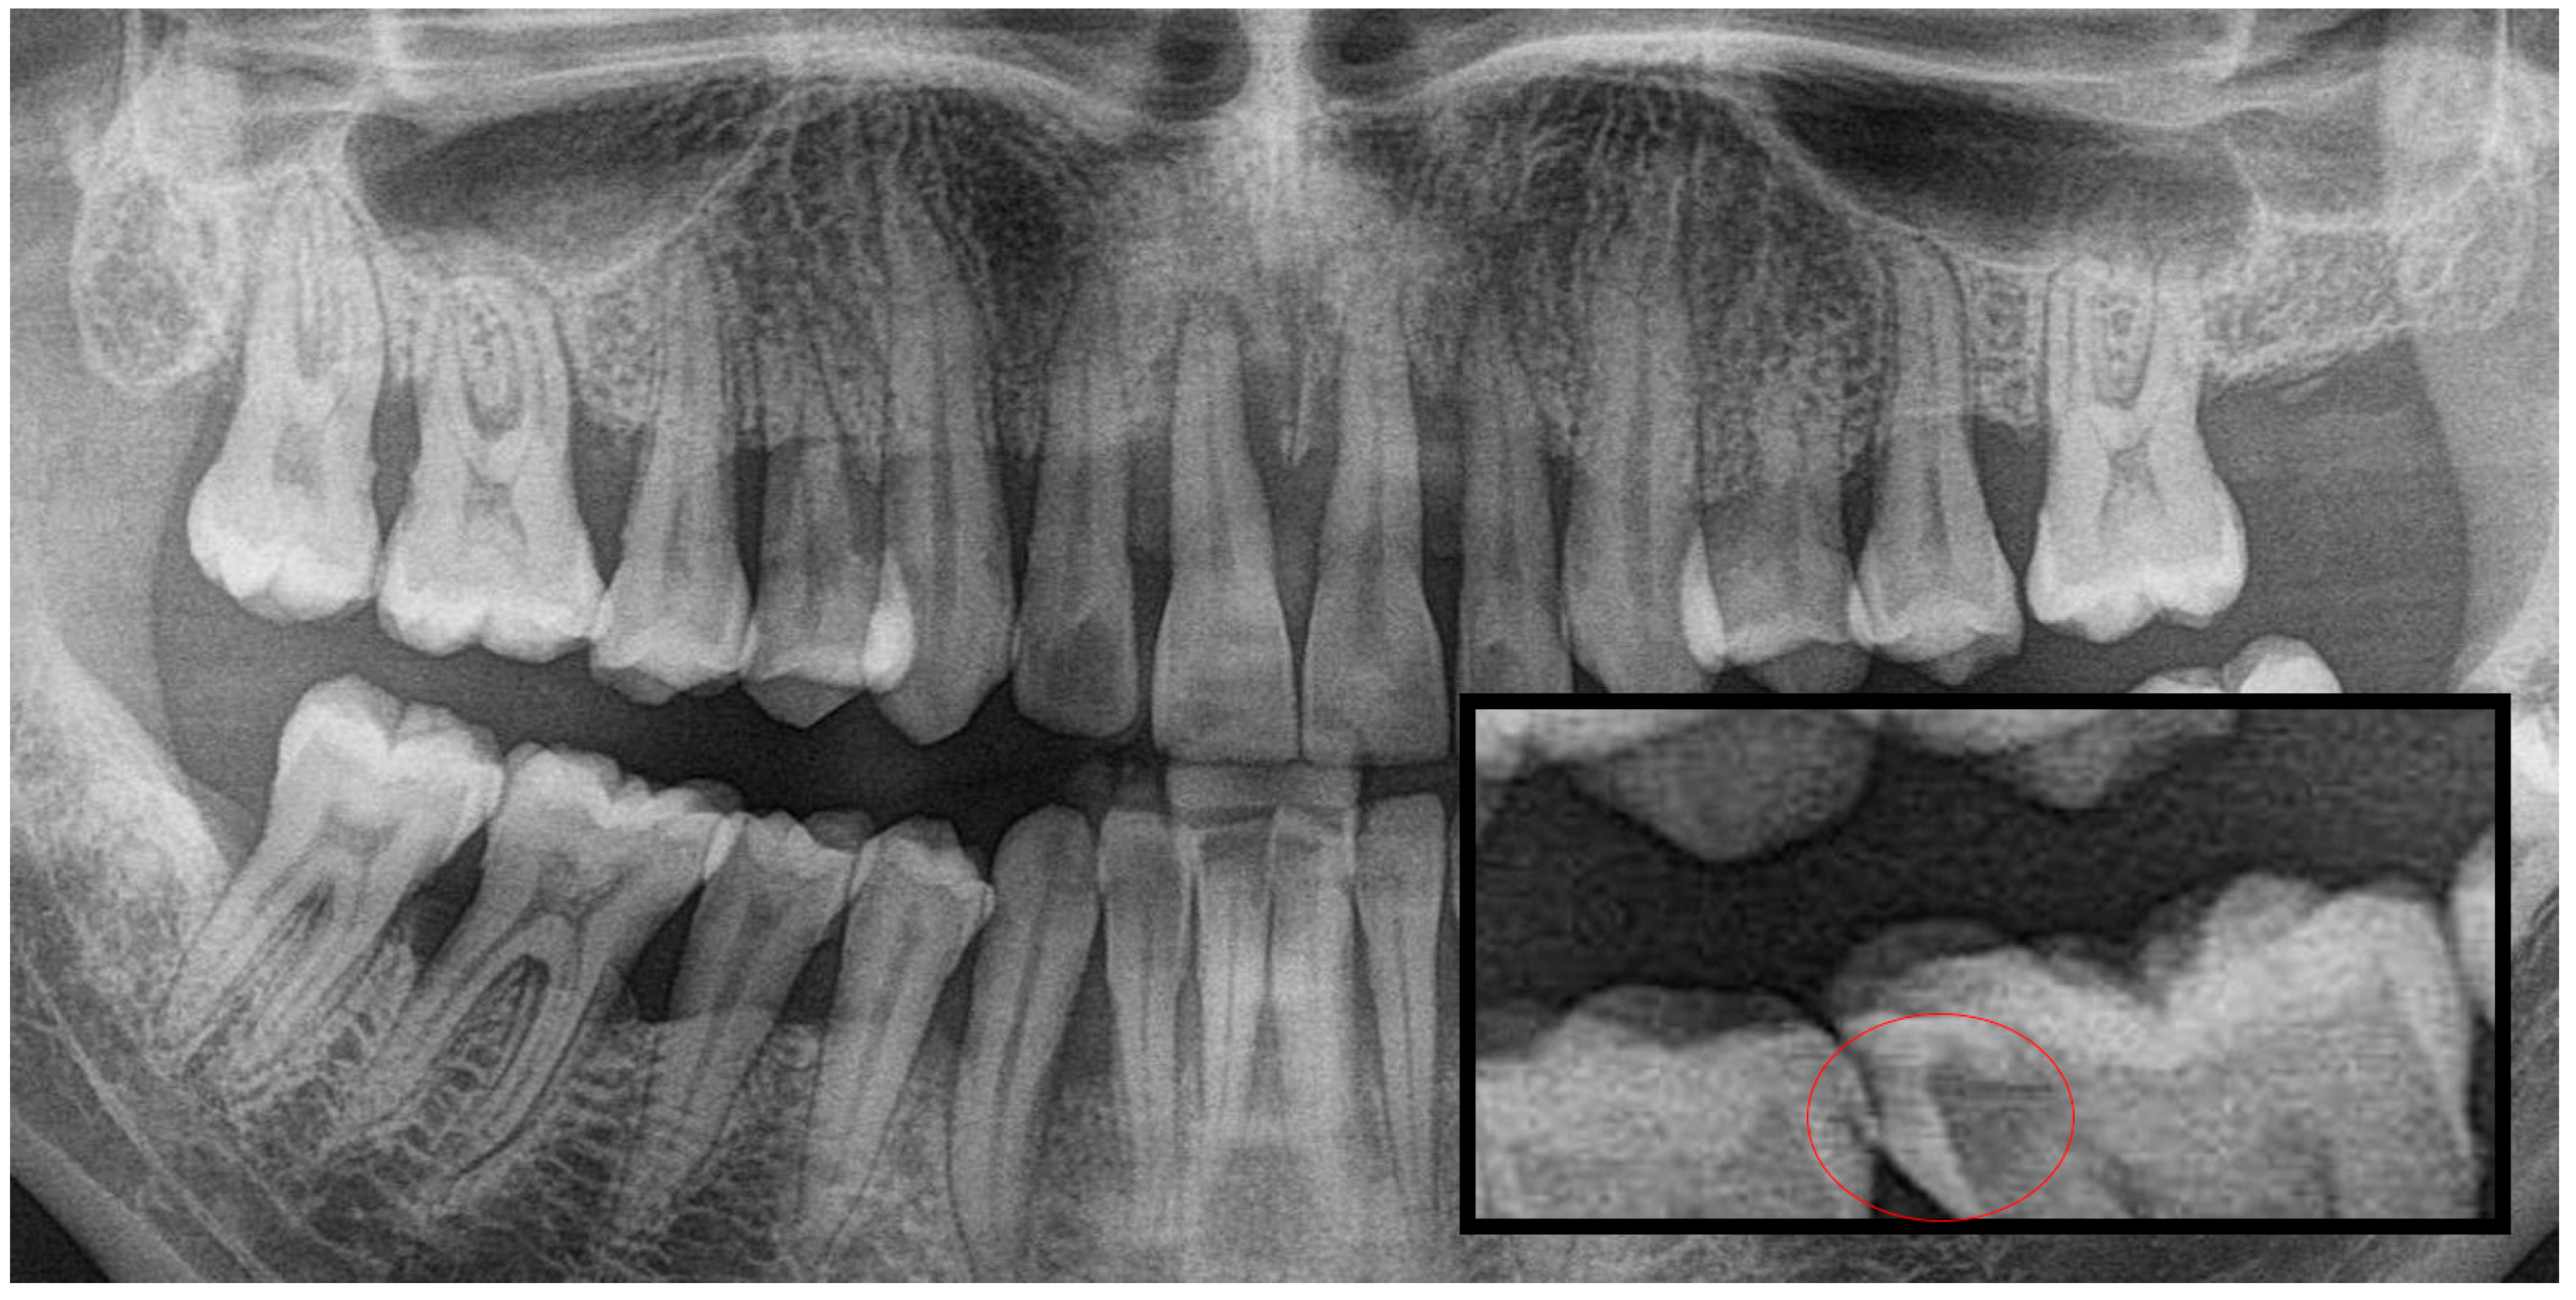

2.1. Evaluation and Categorization of Panoramic Radiographs

2.2. Image Processing and Segmentation